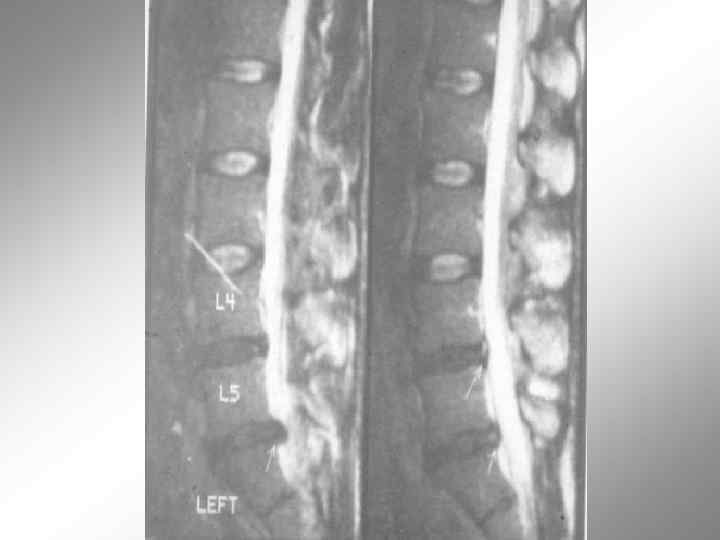

MRT - позвоночника. Спондилит L 2 - L 3 позвонков.